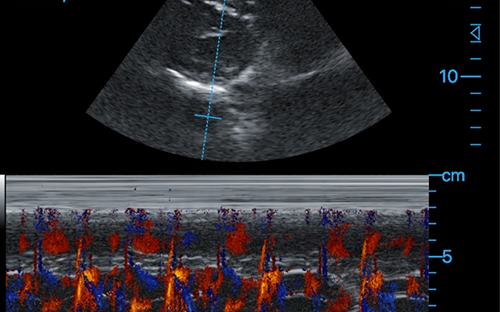

Cardiac + Color M

Cardiac + Color M